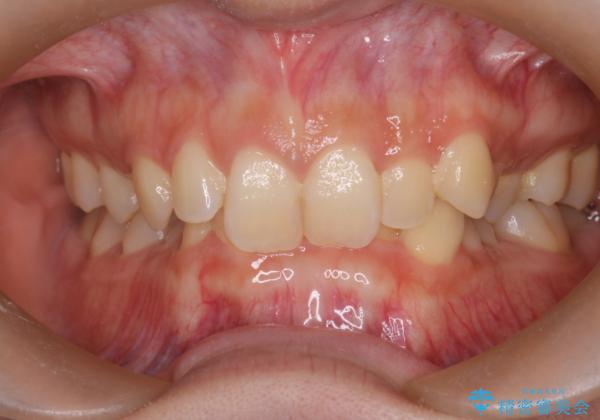

ディープバイト改善のためのインビザライン治療

- 患者様は、全体的な歯列のガタガタとディープバイト(深い噛み合わせ)を主訴として来院されました。診断の結果、ディープバイトを改善するためには、歯列全体の拡大が必要であると判断しました。治療には、透明なマウスピース型矯正装置「インビザライン」を使用し、歯を適切に拡大しながら歯並びを整える計画を立てました。治療期間はおおよそ2年を見込んで進め、最終的に見た目にも大きく変化をもたらすことを目指しました。

ディープバイトの治療には、奥歯の高さや前歯の位置に対する繊細な調整が必要です。本症例では、インビザラインによる歯列拡大を行うことで、噛み合わせを改善し、歯並び全体を整えました。治療過程では、歯間のスペースを確保するため、IPR(インタープロキシマルリダクション)を適宜行い、無理なく歯列の調整を行いました。治療後は、歯並びが大きく改善され、患者様の見た目にも大きな変化が現れました。インビザラインは透明で目立たず、治療中の見た目を気にされる患者様にも配慮した治療法です。